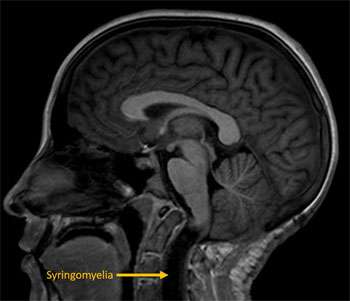

No. In children who do not have any symptoms, we prefer to observe these patients with close clinical follow-up and serial MRI imaging to ensure that the Chiari does not progress. In children who are not symptomatic but show signs of worsening cerebellar herniation, development or progression of syringomyelia or early hydrocephalus, we suggest a strong consideration for surgical treatment. In children that are symptomatic from a Chiari, we recommend surgical treatment. The recommendation for surgery will always be made after careful consideration of the risks of surgery in balance with the risk of not performing surgery.

Possible complications of Chiari can include conditions such as hydrocephalus in which there is excess accumulation of brain and spinal fluid in the head and the development of syringomyelia in which a cavity of brain and spinal fluid develops within the spinal cord. Chiari malformations can also be commonly associated with a tethered spinal cord. This condition results from an abnormal attachment to the bottom of the spinal cord to the bottom of the spinal canal in which the spinal cord is at risk for a “stretch-injury”.

Other tests that we commonly perform may include a sleep study to evaluate for abnormal breathing patterns, a spinal MRI to look for syringomyelia, a thin cut MRI to look for adhesions that are resulting in hydrocephalus or syringomyelia, a CSF flow study to evaluate the flow of brain and spinal fluid at the level of the foramen magnum, and a 3 feet x-ray to evaluate for scoliosis.

There are many different types of surgery being offered for Chiari malformations all of which include removing the bone at the base of the skull as well as part of the first spinal segment. These operations have varying probabilities of success. In general, our approach has been to remove the compressing bone, open the underlying dura (covering of the brain), microscopically release the adhesions and suture in a patch to create more space at the back of the head to ensure normal flow of brain and spinal fluid. In our experience, we have had excellent success rates in successfully treating Chiari malformations with only one operation. This operation ensures us that all our surgical goals can be accomplished. The decision to open the dura may be made upon a number of factors including the child’s age, symptoms and the presence or absence of syringomyelia. We encourage you to discuss the various operations with your neurosurgeon during your consultation.